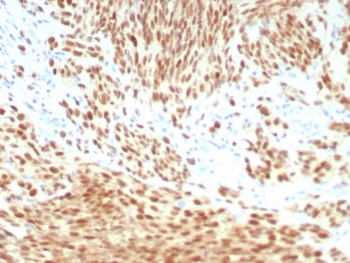

PRAME Antibody Melanoma IHC. Immunohistochemistry analysis of FFPE human melanoma tissue stained with recombinant rabbit monoclonal PRAME antibody clone PRAME/8558R. Tumor cells demonstrate strong nuclear HRP-DAB brown staining consistent with expression of Preferentially expressed antigen in melanoma / PRAME, a cancer-testis antigen involved in tumor-associated immune signaling and transcriptional regulation pathways. The observed staining pattern is consistent with established PRAME expression in melanoma-associated tumor cell populations. HIER: boil tissue sections in pH 9 10mM Tris with 1mM EDTA for 20 min and allow to cool before testing.